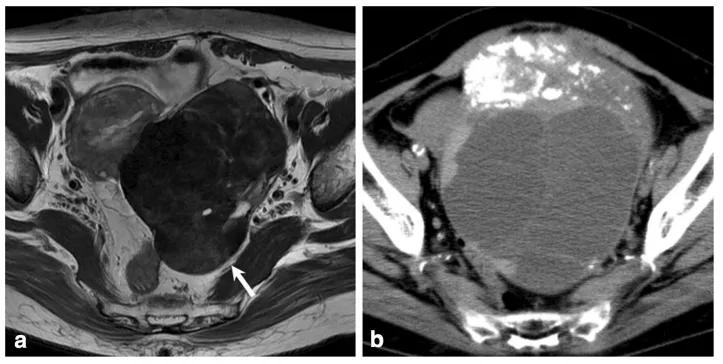

女,34 岁,胃癌双侧卵巢转移瘤。T2WI 显示双侧卵巢实性肿瘤,T2WI 呈高低混杂信号(图 a),DWI 呈高信号(图 b)。